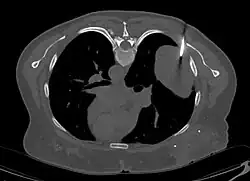

En tomodensitométrie[20],[31], quelle que soit la localisation, une tumeur fibreuse solitaire apparaît comme une masse tissulaire ovoïde ou lobulée, bien délimitée, refoulant les structures voisines sans les envahir. Elle se rehausse fortement après injection de produit de contraste. Les tumeurs de petite taille sont homogènes, mais les plus volumineuses présentent des plages hétérogènes de nécrose et d'hémorragie intra-tumorale. Il n'y a pas habituellement de calcifications et, lorsqu'elles sont présentes, elles sont de petite taille[31]. Les tumeurs malignes peuvent se présenter accompagnées de nodules pulmonaires métastatiques, et tendent à être plus volumineuses et plus hétérogènes[42].